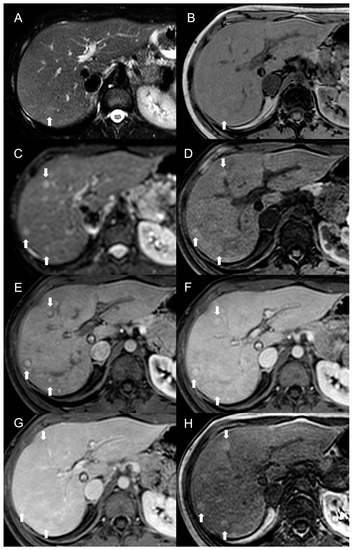

Figure 7.

MRI examination of a 49-year-old female patient with Budd–Chiari syndrome reveals multiple lesions, including two large FNH-like RNs (arrows) in V-VI liver segment. On fat-saturated T2-weighted images (A), these nodules are iso-hypointense with an inhomogeneous central hyperintensity and a low-signal perinodular rim. On T1-weighted images (B) the FNH-like RNS appear hyperintense, one of them exhibiting a central hypointensity corresponding to the central scar. In DWI (b-value = 600) (C), they show the same signal intensity as the adjacent liver parenchyma, with appreciable low-signal peripheral rim. On T1-weighted unenhanced (D), arterial (E), portal (F), and delayed (G) phase images, the FNH-like RNs demonstrate inhomogeneous arterial enhancement and isointense signal on the portal and delayed phases; the hypointense perinodular rim, representing congested hepatic tissue, remains noticeable. In the hepatobiliary phase (H), the FNH-RNs display inhomogeneous iso-hyperintense signals compared to the surrounding liver parenchyma. A third lesion, compatible with a hemangioma (arrowhead), is also visible, showing homogeneous hyperintensity on fat-saturated T2-weighted images (A) and DWI (b-value = 600) (C), hypointensity on T1-weighted images (B), slow centripetal globular enhancement on arterial (E), portal (F), and delayed phase (G) images, and hypointense signals in the hepatobiliary phase (H).